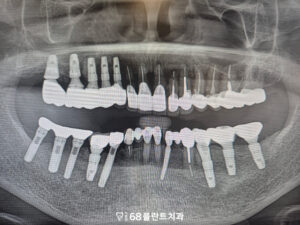

먼저 손상된 치아들을 전부 발치한 뒤,

오른쪽 부위부터 순차적으로

치료를 진행하였습니다.

해당 부위의 잇몸뼈 상태를

확인한 후,

안정적인 고정을 위해

임플란트를 먼저 식립하였으며

이후 회복 기간을 거쳐

최종 보철을 제작하였습니다.

이렇게 오른쪽 부위를 먼저 완성하여

치료 기간 동안에도

식사를 비교적 편하게

하실 수 있도록 하였으며,

이후 반대쪽 부위 역시

같은 방식으로 치료를

이어 진행하였습니다.